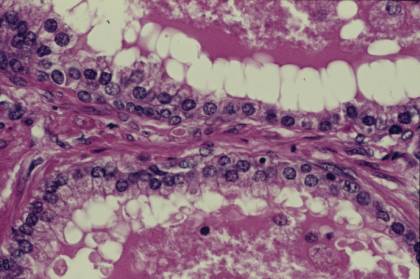

ヒト、ブアン液で固定、パラフィン包埋、H-E染色、x 500.

「精巣34」の拡大。前立腺の腺腔を囲む上皮は単層または2列の円柱--

上皮細胞で、細胞の丈は機能状態によって立方状から丈の高い円柱状--

の間で変化する。腺と腺の間の結合組織の中には多量の平滑筋繊維が--

存在する。-------------------------------------------------------------------------

Human, fixation with Bouin’s fluid, embedding with paraffin, H-E stain, x 500.

Higher magnification of “Testis 34”. The epitheliar cells encircling the-------

lumen is simple columnar or pseudostratified columnar of 2 rows of nuclei.

Form

and hight of cells change between high columnar and low cuboidal---

according

to the functional state. In the interstitial connective tissue there-

are a lot of smooth muscle fibers.------------------------------------------------------